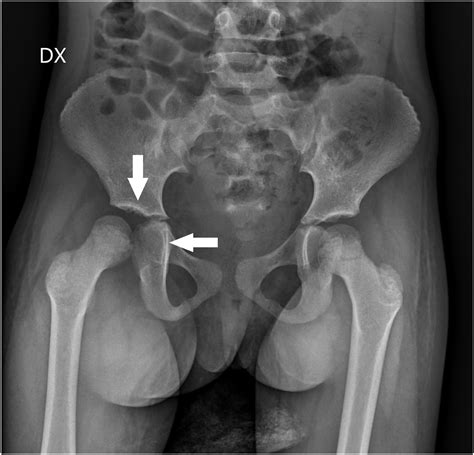

To determine the cause of your hip pain, a healthcare professional will conduct a thorough physical examination followed by diagnostic imaging. Because many conditions mimic the symptoms of hip joint effusion, accurate imaging is essential. Below is a breakdown of the common diagnostic tools used:

X-ray To rule out fractures or severe osteoarthritis.

• hip joint effusion x ray